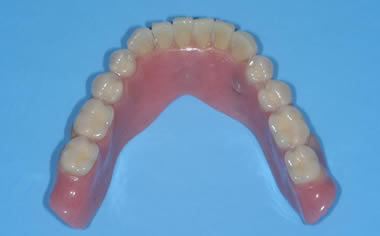

Loose dentures secured by dental implants

Case One (5 images)

Three dental implants used to secure a loose lower denture.